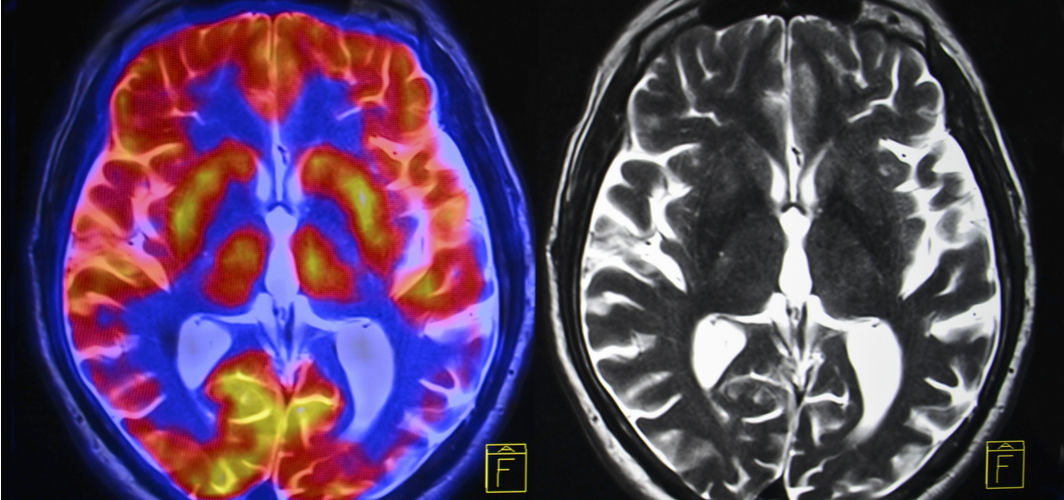

Transient ischemic attack or cerebrovascular accident, commonly called stroke, occurs when the blood flow to the brain is blocked. This prevents the brain from getting an adequate supply of oxygen and nutrients from blood, increasing the risk of brain cell death within minutes.